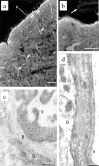

Fig. 5.

a, b, Immunofluorescence labeling of AQP4 in a cortical slice treated with vasopressin. a, Strong AQP4 immunolabeling of the glia limitans (double arrows) facing the unlabeled pia, and of glial end feet surrounding the blood vessels (short arrows). p, Pia. b, Higher magnification showing an unlabeled pial vessel (arrow). Scale bar, 20 μm. c, d, Immunogold labeling of AQP4. c, AQP4 labeling of glial end feet surrounding a collapsed vessel in a cortical slice treated with vasopressin. d, Electron micrograph showing AQP4 labeling of glia limitans facing a pial vessel in rat parietal cortex.V, Vessel lumen; B, basal lamina;G, glial process. Scale bar, 0.3 μm.